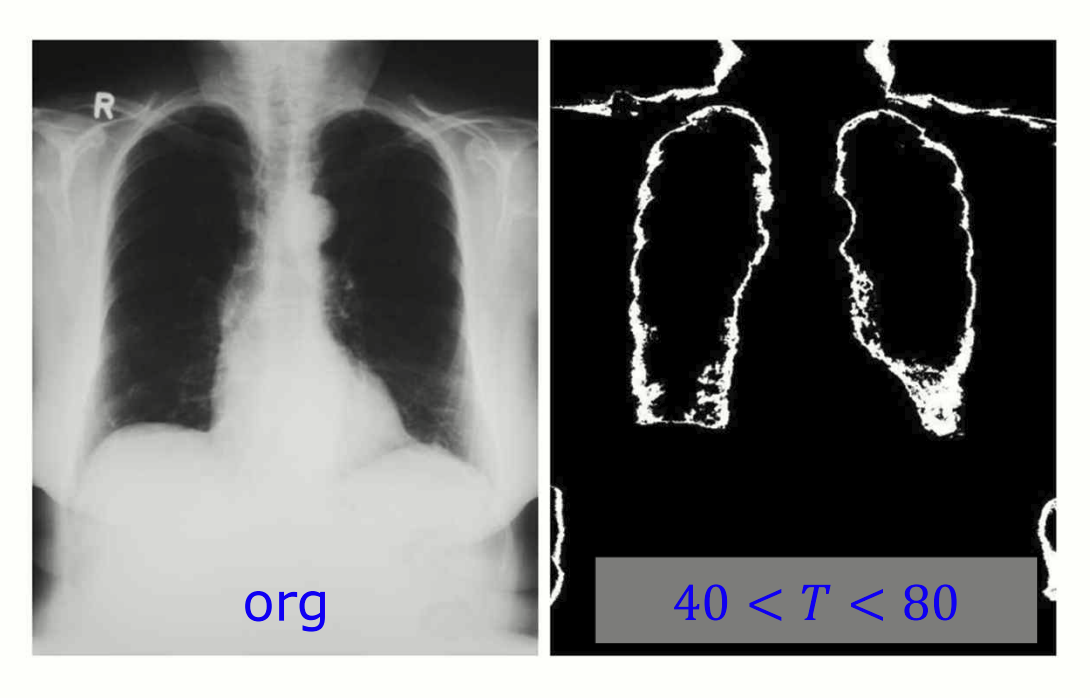

두 가지 임계값 T 를 설정하면 더 정교하게 segmentation 을 수행할 수 있습니다.

환자의 폐를 double thresholding 을 통해 segmentation 한 이미지.